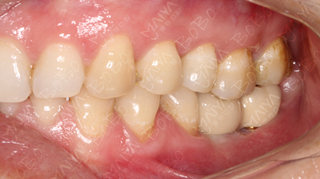

种植完成后的牙齿情况